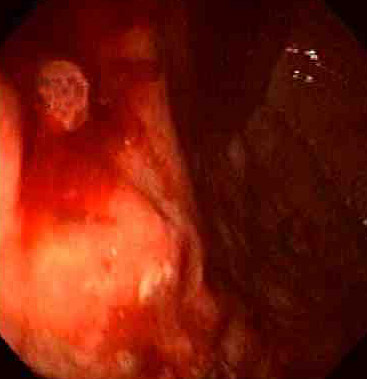

On upper GI endoscopy above is an area of angiodysplasia. This condition, more common in older persons, is a cause for GI tract bleeding. One or more foci of irregular dilated venous or capillary channels are present in the submucosa, typically of the colon, but occasionally elsewhere. The lesions are often quite small, less than 0.5 cm, making them hard to find. Colonoscopy and mesenteric angiography can be performed for diagnosis. The histologic appearance is shown below, with multiple dilated vessels in the lamina propria and submucosa. |